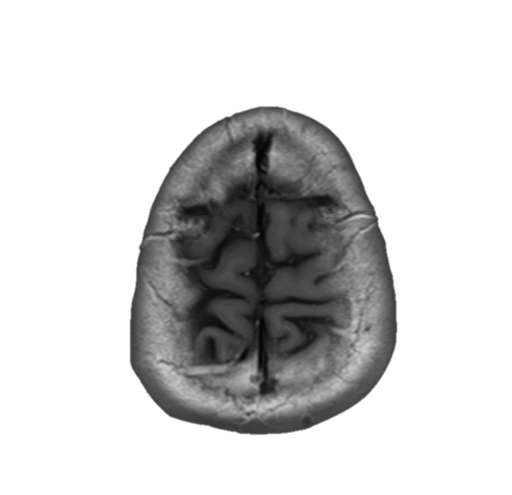

中心溝、中心前溝、中心後溝、中心前回、中心後回のMRI画像における解剖

主に脳梗塞診断などで重要な中心溝、中心前溝、中心後溝、中心前回、中心後回のMRI画像における解剖(CTでも使えます。)をご覧いただけます。